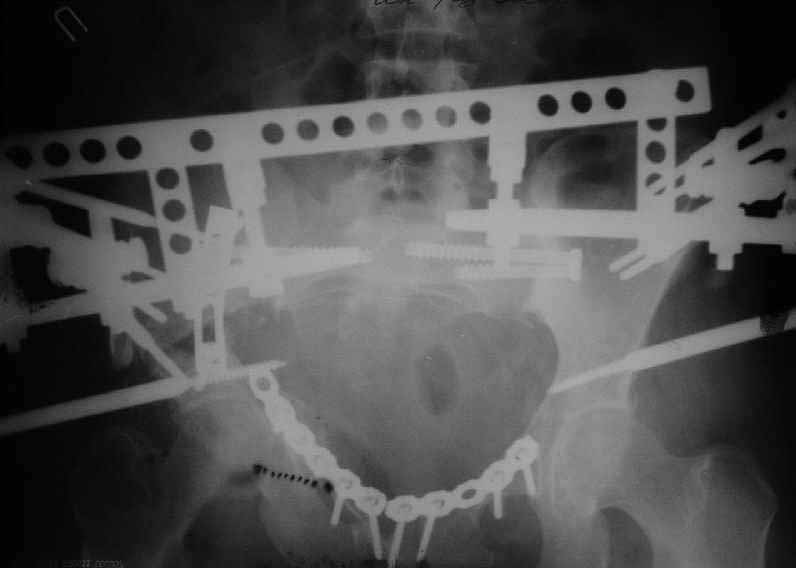

On Jan 26, 2005 the right wing was osteotomized, its segment with the

acetabulum was moved downwards, the ilium was plated, and pelvic external

fixator with femoral extension applied (left image).

After wound healing, anterior reconstruction was performed, iliosacral

screws inserted, the femoral frame removed.

To date wounds healed, the patient walks with crutches, no

weight-bearing at the right side (rest images).

I hope that she'll be better...it's hard to see much on the images with the frame structure on it.